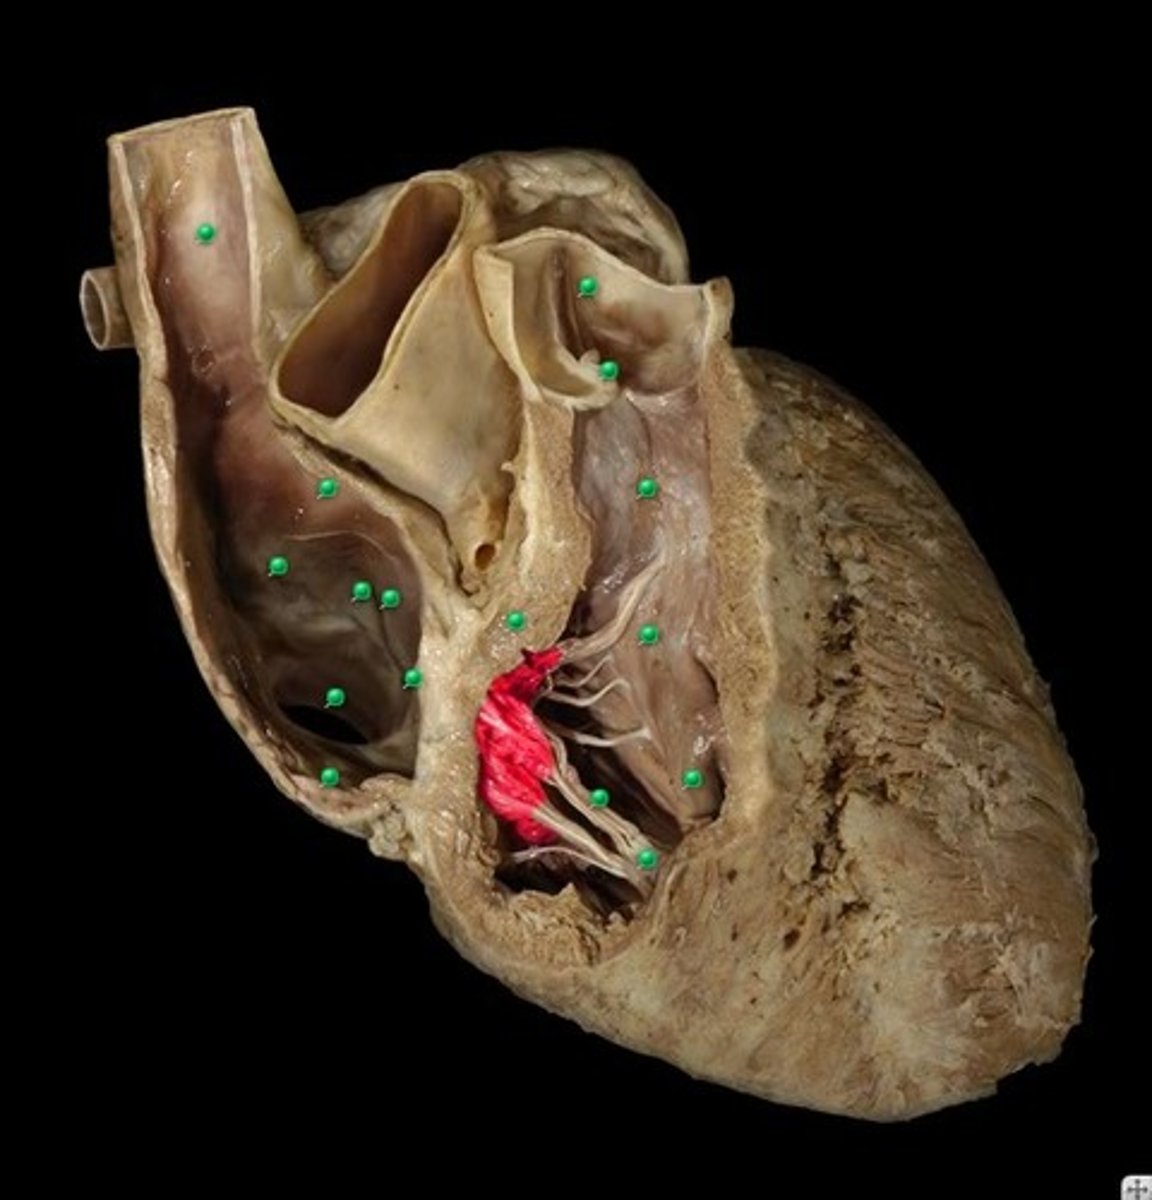

Bicuspid valve/Mitral Valve/Left atrioventricular valve

right atrioventricular valve/tricuspid valve